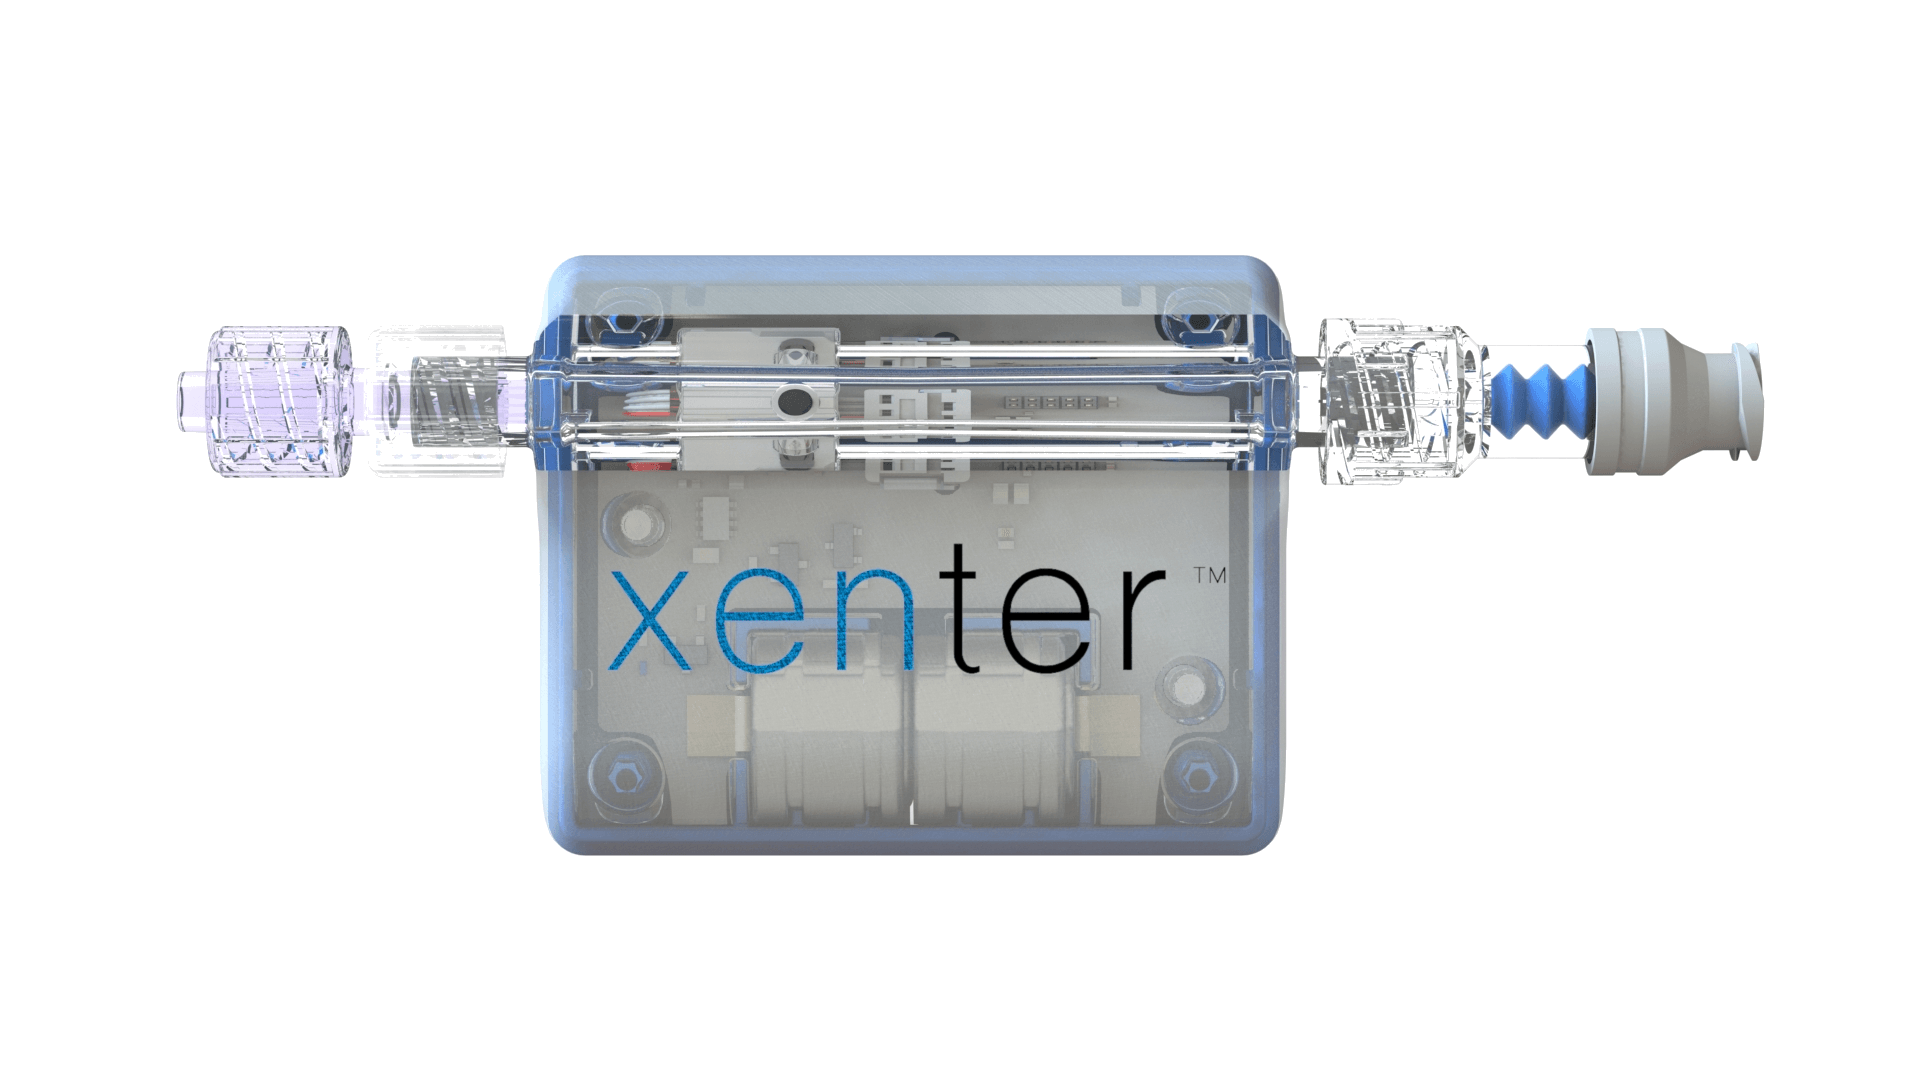

Smart Devices

Smart, wireless medical devices

Xenter devices gather Physical Intelligence data from the clinical environment

XenFi™

Wireless Network

Physical Intelligence data from smart devices is transmitted through the Xenter XenFi™ wireless network to EHRs and XMD™.